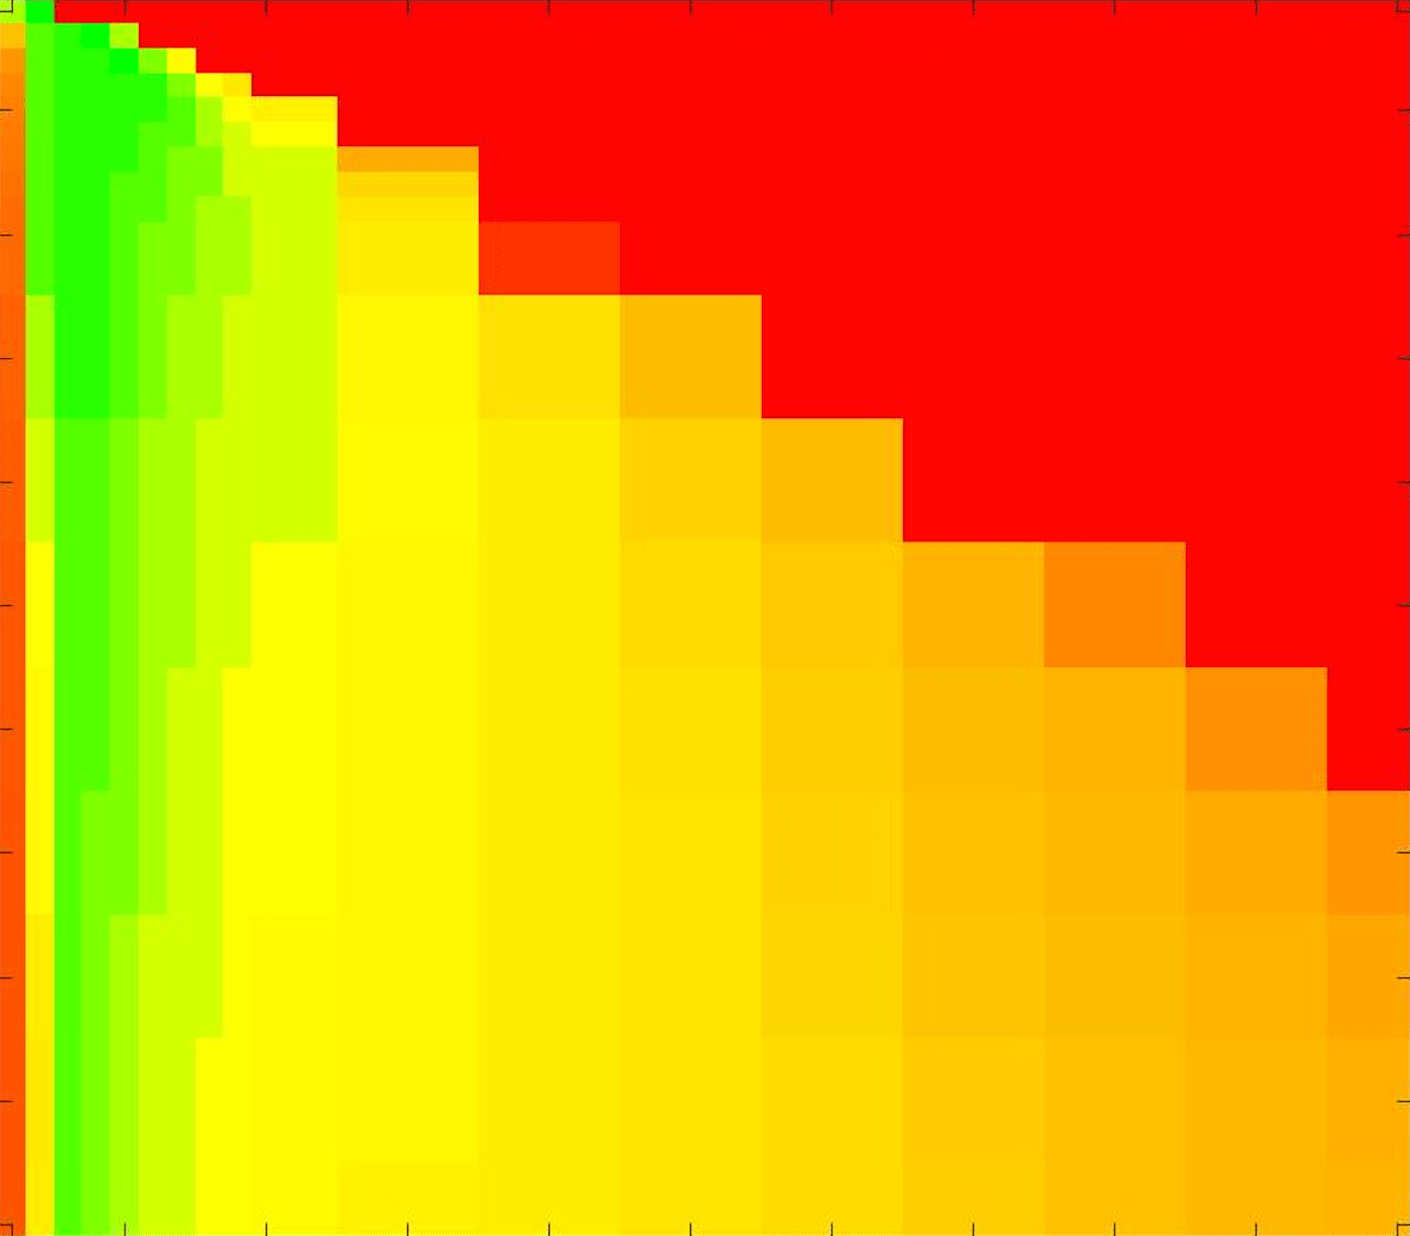

where refers to the number of points in the enclosed region. This takes values in the range , with higher TC values indicating a more accurate segmentation. In the following we will represent accuracy visually from red () to green (), with the intermediate scaling of colours used shown in Fig. 8. This will be particularly relevant in §7.2.

The TC values for the parameter sets are presented as heatmaps in Figs. 11–13. A heatmap is a convenient way to display accuracy results for hundreds of tests concisely. In Fig. 9 we give an example heatmap with the same axes used for those in Figs. 11–13. For each of the combinations of parameter values we give the TC value of the segmentation result and represent it by the appropriate colour. The corresponding colour scale is shown in Fig. 8. Qualitatively, the more green areas of the heatmap the more accurate the model is for a wider set of parameters. Example results for Test Image 5 when varying (with ) for the proposed model are given in Fig. 10. Here it can be seen what each accuracy result corresponds to visually.

Note. The axes have been removed from the heatmaps in Figs. 11–13 for presentational clarity. However, to be explicit, the axes used in all heatmaps are the same as those in Fig. 9.

Synthetic Images. These results are presented in Fig. 11. For Test Images 1–2 we see poor parameter robustness from all competing models, except for GAV which performs reasonably well. However, the proposed model has minimal parameter sensitivity for these images, with good results achieved for almost every combination of values tested. For Test Image 3 all models have a reasonable parameter range (except for RSF), however the proposed model gives better quality results for a wider parameter range. The other models achieve reasonable results here as the foreground intensity of the ground truth is greater than the background , whereas for Test Images 1–2 they are equal . These results highlight the key advantage of the proposed model.

Real Images. In Fig 12 we present results for Test Images 4–6. Here, the proposed model performs in a similar way to its competitors because these images are more typical selective segmentation problems in the sense that there is a clear distinction between the foreground and background intensities. In particular, the values in each case are: Test Image 4 , Test Image 5 , and Test Image 6 . It can be seen that the proposed model is competitive compared to previous approaches. The performance is quite poor for Test Image 5, but is arguably still the best for this challenging case. In Fig. 13 we present results for Test Images 7–9. Here the proposed model outperforms previous approaches significantly for each image. This is mainly due to the type of image considered. Specifically, the true intensities are: Test Image 7 , Test Image 8 , and Test Image 9 . The proposed model is capable of achieving results where , with other models failing completely in these cases.